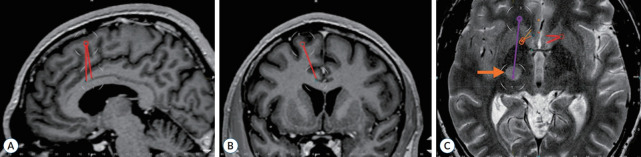

Stereotactic bilateral anterior cingulotomy, including lesions in the anterior and midcingulate cortex, is one of the methods used for treating thalamic pain syndrome. In cases of non-ischemic thalamic lesions, simultaneous stereotactic biopsy of the lesion can be performed in combination with cingulotomy. In this paper we present a case of a 45-year-old male with a lesion in the right thalamus, causing a severe contralateral hemi-pain syndrome. Bilateral radiofrequency anterior cingulotomy and stereotactic biopsy were performed during a single surgery. Pain completely subsided within a few days following the anterior cingulotomy. Histological examination identified a diffuse astrocytoma (World Health Organization grade II, ICD-O 9400/3), and the patient was subsequently referred for LINAC-based radiosurgery. The pain syndrome was controlled for 4 years, after which the pain syndrome returned with an increase in tumor size. Simultaneous anterior cingulotomy and stereotactic biopsy of the thalamic lesion represent a safe intervention for thalamic pain syndrome, enabling the alleviation of pain, verification of the lesion's etiology, and the application of appropriate treatment.

Abstract Image